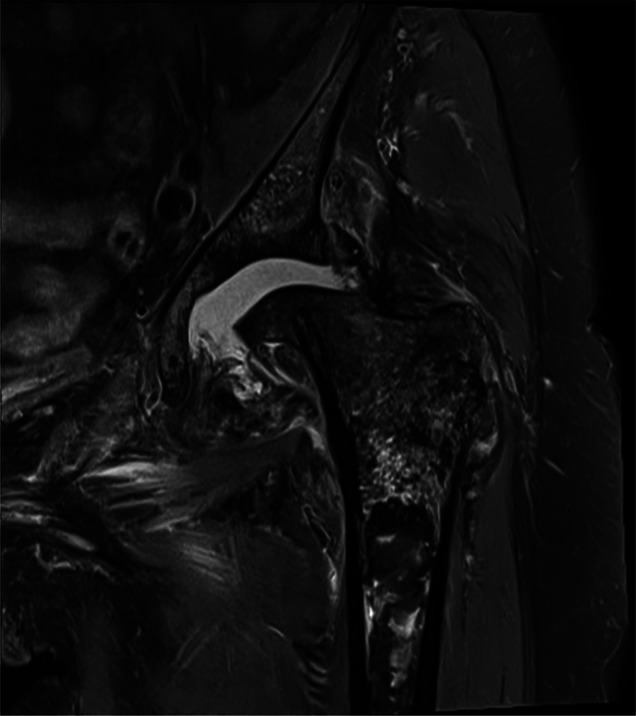

摘要非外伤性双侧股骨头坏死(ONFH)是一种罕见的现象,其病因尚未完全了解。在本报告中,我们描述了一例75岁的女性患者,在关节内皮质类固醇注射后发展为快速发作的双侧ONFH。患者接受分阶段双侧全髋关节置换术。术后几个月,患者出现左侧股骨假体无菌性松动,需要对其股骨假体进行翻修。在最初的手术处理中,她的骨坏死的严重程度和远端程度并没有得到充分的认识,这可能增加了她股骨植入物骨整合失败的风险。本病例表明,关节内皮质类固醇注射可导致严重的ONFH,并延伸至股骨近端并导致固定失败。因此,股骨近端骨坏死的程度可能影响茎的选择。

Atraumatic bilateral osteonecrosis of the femoral head (ONFH) is a rare phenomenon whose etiology is not fully understood. In this report, we describe the case of a 75-year-old female patient who developed rapidly onset bilateral ONFH after intra-articular corticosteroid injections. She was treated with staged bilateral total hip arthroplasty. Several months post-operatively, she developed aseptic loosening of the left femoral implant and requiring revision of her femoral implant. The severity and distal extent of her osteonecrosis was not fully appreciated upon initial surgical management, likely increasing her risk of failure of femoral implant osseous integration. This case demonstrates that intra-articular corticosteroid injections can cause severe ONFH with extension into the proximal femur and fixation failure. Thus, the extent of osteonecrosis in the proximal femur may influence stem choice.